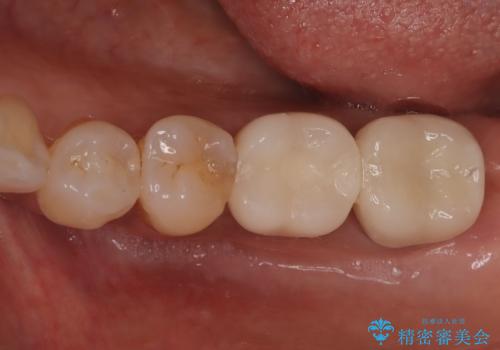

骨の量は十分あったため、比較的短期間で治療は終了しました。

安定した咬み合わせとなり、痛みもなく安心して噛めるようになりました。